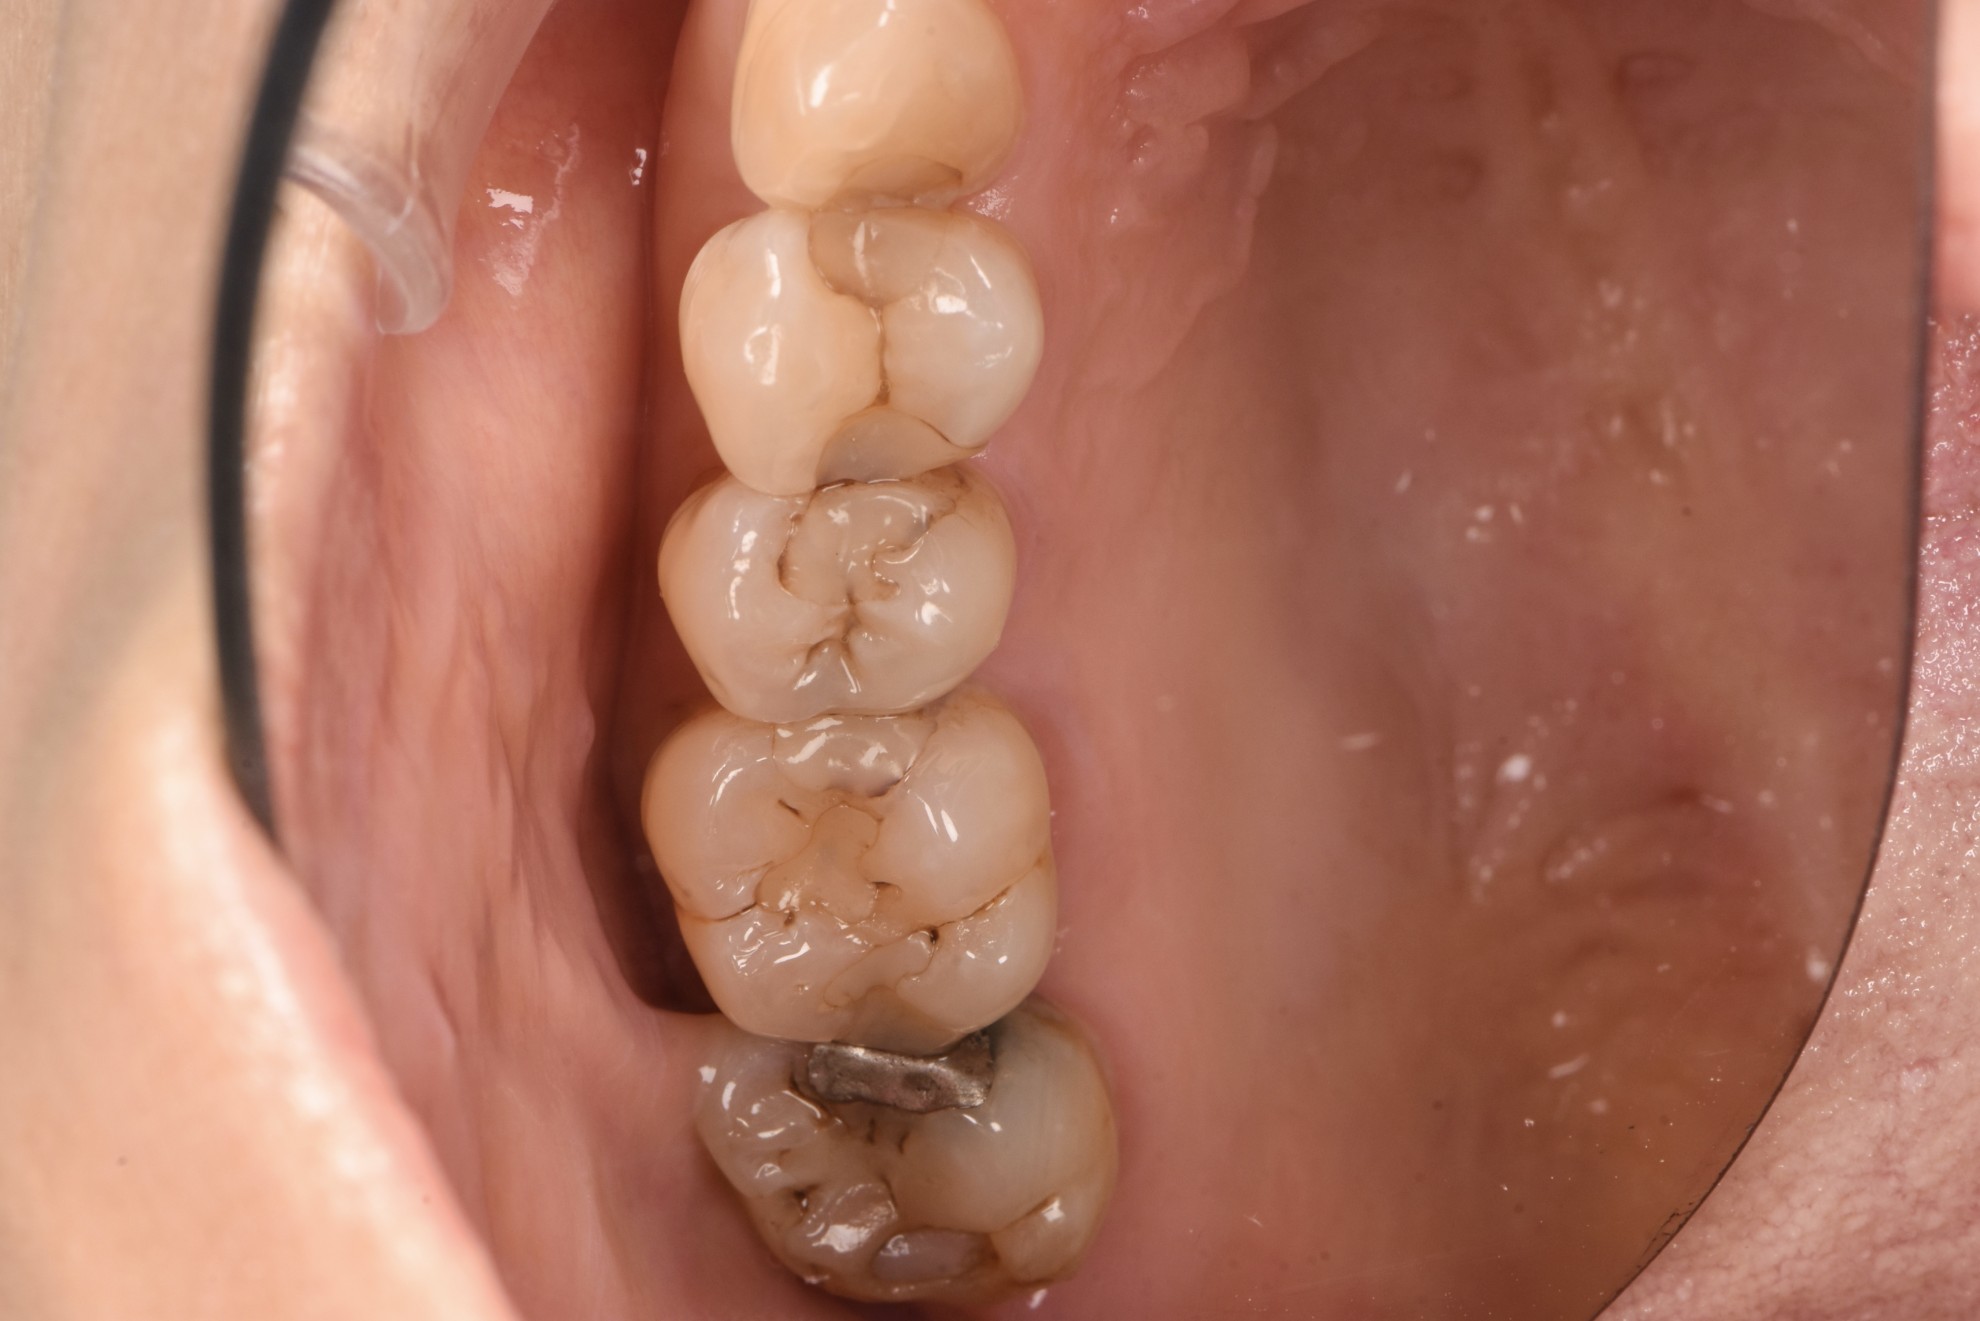

治療前

案例一